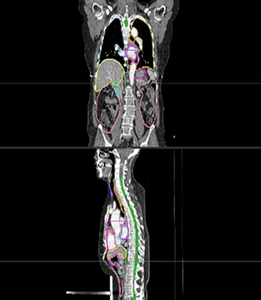

Unit1 차세대 인공지능 기반 환자맞춤형 자기공명영상 유도 방사선치료 기술 개발

딥러닝기반 MR 영상분할 기술 개발

면역 피해 예측 기반 방사선치료기술 최적화